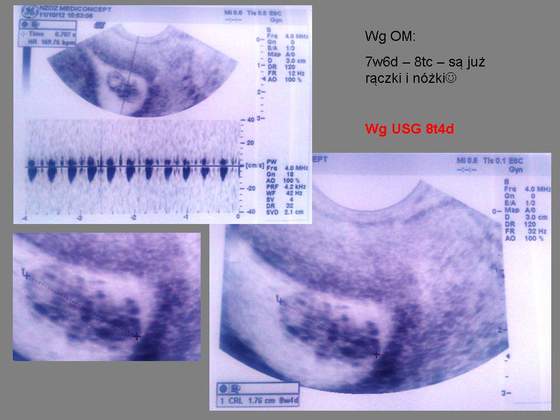

Iownka będzie dobrze. Dbaj o siebie i bądź dobrej myśli.